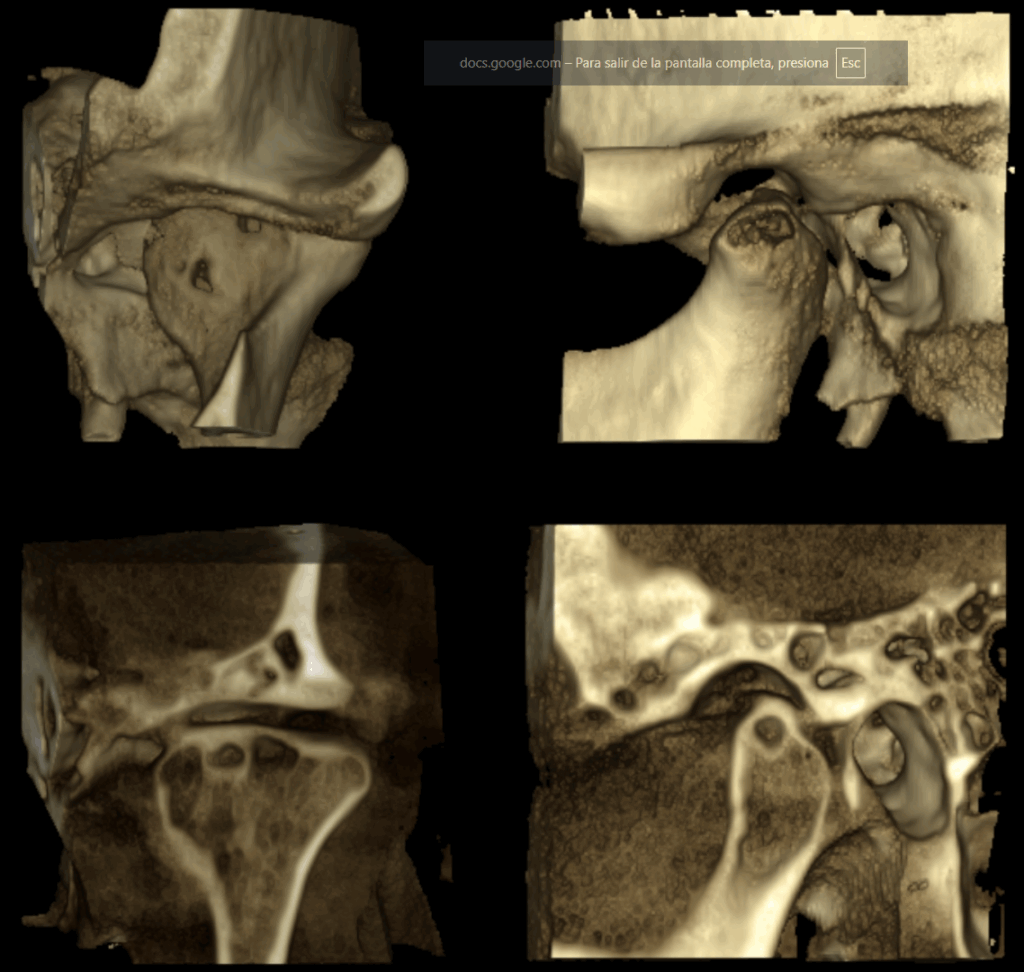

En las reconstrucciones 3D se representa de manera didáctica Quiste Óseo Sub Condral. (Figura 4).

RECONSTRUCCIÓN 3D